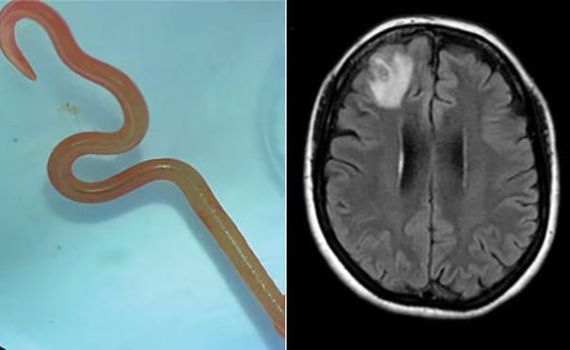

לראשונה אי פעם, תולעת טפילית המוכרת כתולעת המזהמת בעלי חיים, בדגש על נחשים ונחשי פיתון, נמצאה במוחה של אישה בת 64 באוסטרליה.

האישה נלקחה לניתוח חירום, שם הצליחו להגיע הרופאים אל אזור הזיהום, והוציאו ממוחה של האישה תולעת באורך של שמונה סנטימטרים, האישה עברה את הניתוח בהצלחה ומצבה יציב.

התולעת היא תולעת טפילית אשר מוכרת במיוחד בנטייתה לזהם נחשים, בדגש על נחשי פיתון גדולים, זה הוא המקרה הראשון המתועד בעולם של תולעת טפילית מסוג שכזה המתיישבת במוח אנושי.